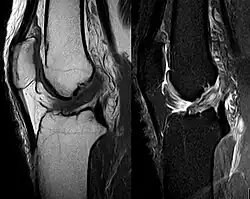

Procédés d'imagerie

Le diagnostic peut être confirmé par imagerie (IRM). Mais il faut noter que l'interprétation de l'IRM seule pour le diagnostic de rupture de LC conduit à 20 % de faux diagnostics. Cela dépend des images de coupe et de la position appropriée du genou pendant l'IRM. Le radiologue doit connaître avec précision les circonstances qui ont conduit à la blessure, et avoir aussi une bonne expérience de l'étude d'une articulation blessée, pour éviter les faux diagnostics. Pour comparer avec l'IRM, le taux d'erreur du test de Lachman, bien plus simple à accomplir, n'est que de 10 %[108],[109],[110],[111]. L'IRM est donc généralement moins sensible et moins spécifique que l'examen clinique par un orthopédiste qualifié[112]. Le résultat de l'IRM n'a que relativement rarement une influence sur la formulation finale du diagnostic[113] et ne devrait pas servir de remplacement pour une anamnèse soigneuse et la palpation[114]. Plusieurs études arrivent à la conclusion que l'IRM n'a de sens que pour des blessures complexes difficiles à expliquer, et là, pour éviter de poser un diagnostic négatif[115],[116],[117].